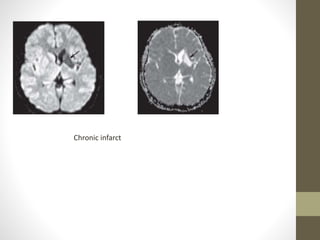

• Chronic infarcts are characterized by elevated diffusion and

appear hypo or isointense on DW images and hyperintense on

ADC maps

Chronic infarct